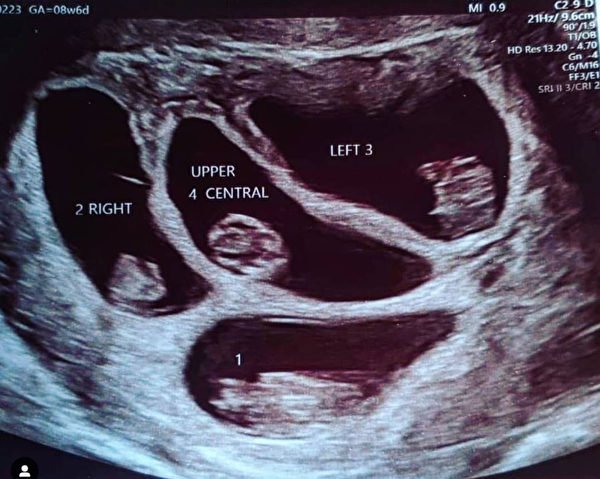

娜塔莉告诉媒体“生活”(That’s Life),“我躺在孕检台上,超声波医师用B超仪为我做检查,我看了一下模糊的屏幕,发现了两个囊。”

纳塔莉欣喜若狂,因为她的家族的确有生双胞胎的家族史。但超声波医师报出的胎儿数目震惊了在场所有的人。她回忆道:“超声波医师一言不发,举起了四个手指。卡恩几乎晕了过去。”